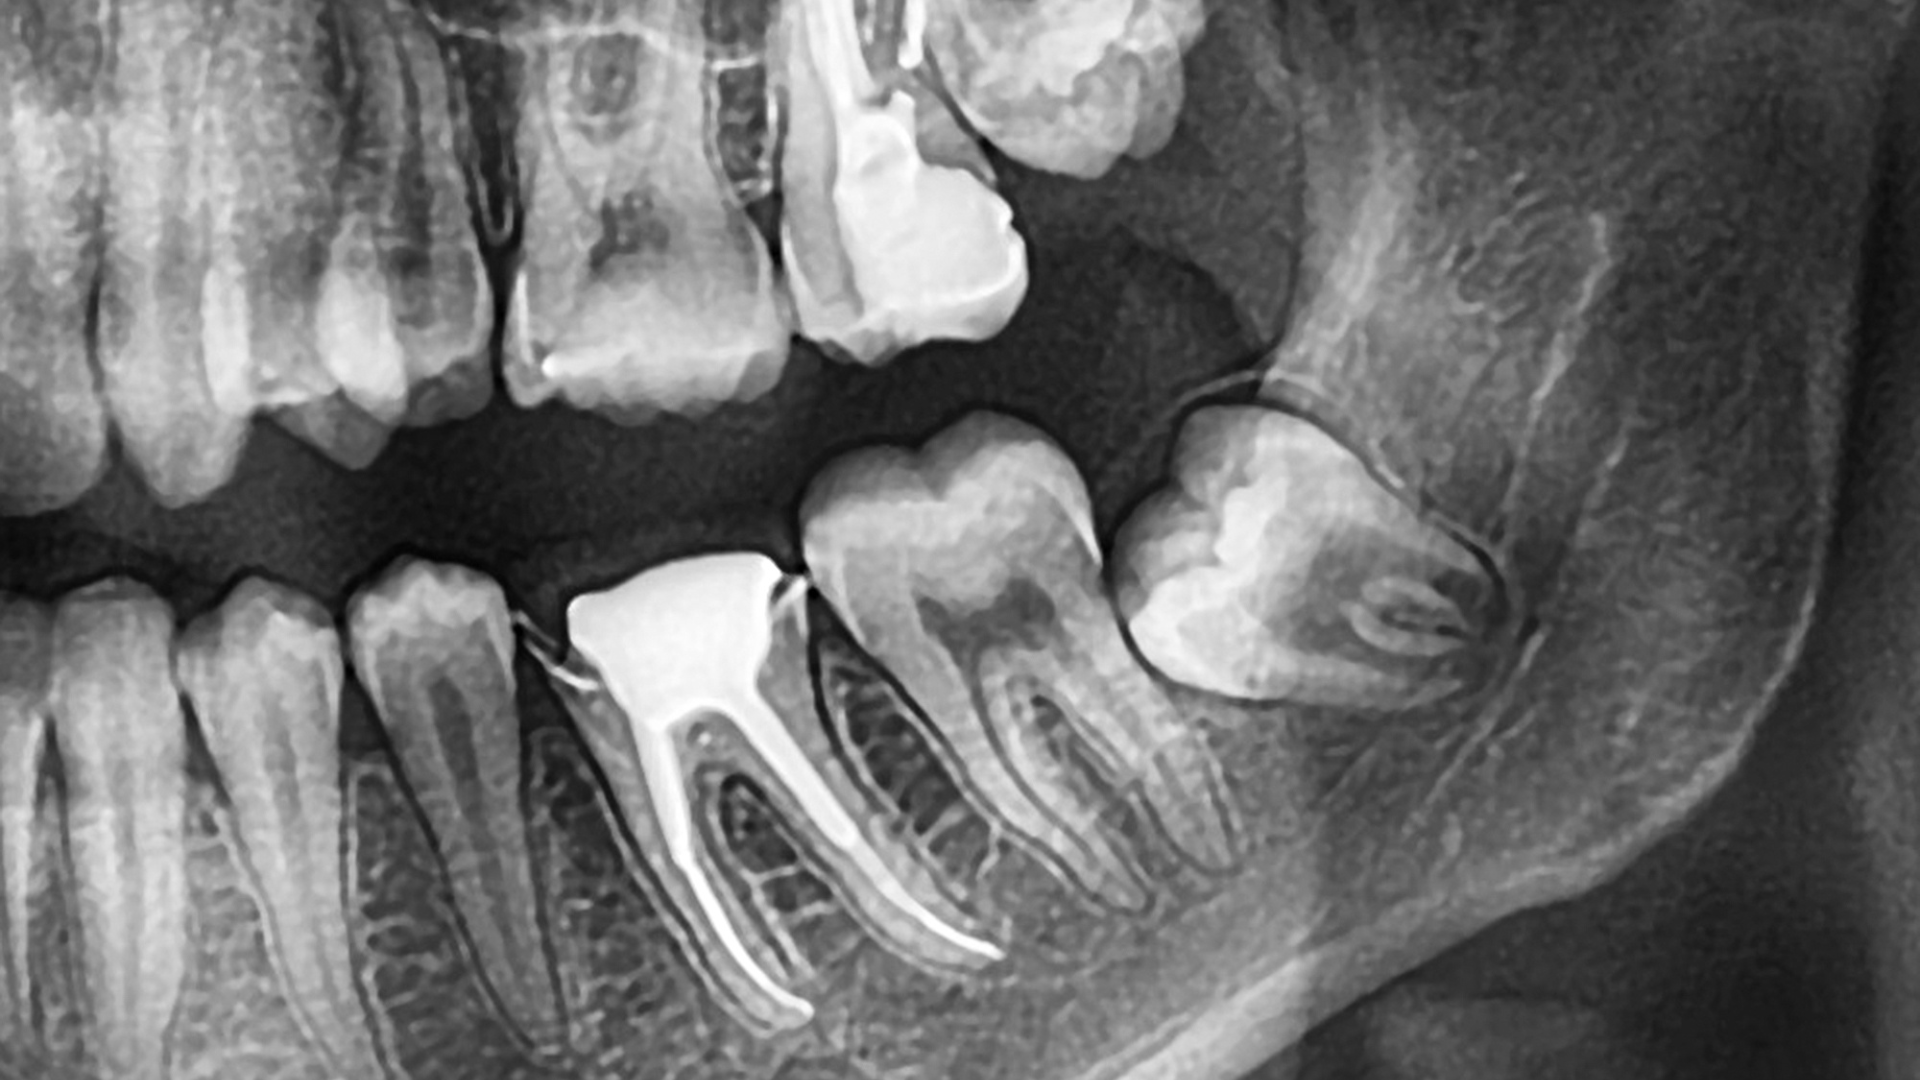

Hình ảnh X-quang giúp xác định:

- Hướng mọc và vị trí răng khôn.

- Mức độ kẹt trong xương hoặc lợi.

- Ảnh hưởng lên răng kế cận.

Đây là bước bắt buộc để tránh đánh giá sai lệch.